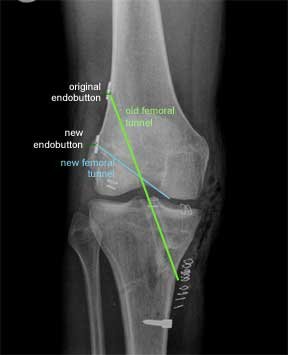

Revision from trans-tibial to 'more anatomic'

This is an X-ray of a patient who had a trans-tibial ACL reconstruction performed in another hospital. This was revised to a ‘more anatomic’ single bundle ACL, when it failed. The old femoral tunnel is highlighted in green and the new femoral tunnel is highlighted in blue.

This X-ray is from the front as before. The original endobutton was not removed. If you follow the line of the new femoral tunnel it is clear that it has been drilled from an antero- medial portal as the blue line points to two skin clips at this point.